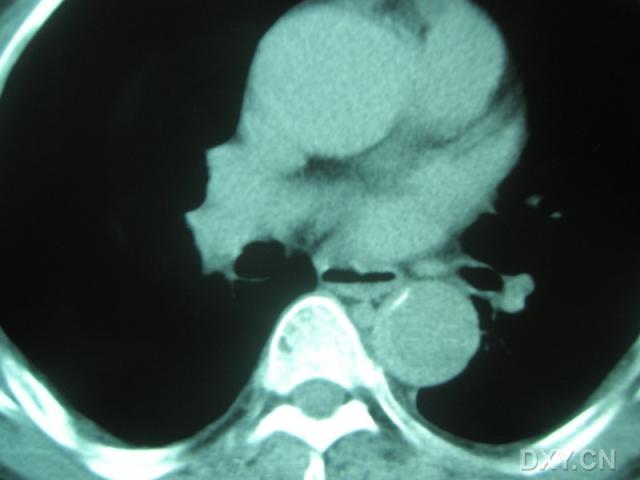

此病例是偶一年前管的一个病人,今来复诊,忽觉得其有一定的代表意义,说给大家,同时期待听到大家的不同声音,来促进学习。 患者某某,男,65岁 以“突发钻顶样胸背痛2小时”为主诉入院。 患者两小时前于情绪激动后突发钻顶样后背痛,疼痛一开始即达高峰,难一忍受忍,轻微走动后旋即又出现前胸部疼痛,性质相同,持续不缓解,伴出汗,恶心,未吐,无黑朦晕厥,无肢体活动障碍,急来我院。急诊行胸部CT后(下图),收入病房。 既往史:高血压病史10余年,最高血压180/100mmHg,未系统用药及检测。否认糖尿病史及冠心病史。有大量吸烟史,至少400年支,无药敏史。 入院时PE: T 36. 5° P 80次/分 R 22次/分 BP 180/95mmHg,其他查体未见阳性体征。 化验:CRP升高(11.8mg/L),WBC 10.3×109/L,肝、肾功,血糖、离子,血淀粉酶等正常。 心电图未见异常。急行床旁超声:主动脉瓣轻---中度返流,左室内假腱索,各心房心室不大,EF值:55% 入院后考虑主动脉夹层,紧急予以硝普钠降压,拜新同、依那普利联用口服降压,美托洛尔减弱心肌收缩力及控制心率,吗啡对症止痛,仍持续疼痛,最后经患者家属签字同意后紧急行主动脉增强CT(下图)。后疼痛逐渐缓解至平稳。 平扫CT报告:主动脉增宽,内密度不均,建议增强 增强CT:自主动脉起始部至腹腔干水平,主动脉影增宽,注药增强过程中,管壁无强化。也没有发现内膜撕裂及假腔。 请教: 您考虑的诊断?治疗? 对本病例诊治的异议?